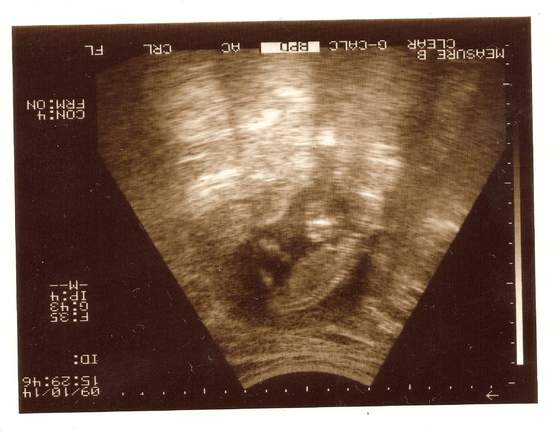

sandra -miałaś usg?? wklej zdjecie dzidziusia:-)